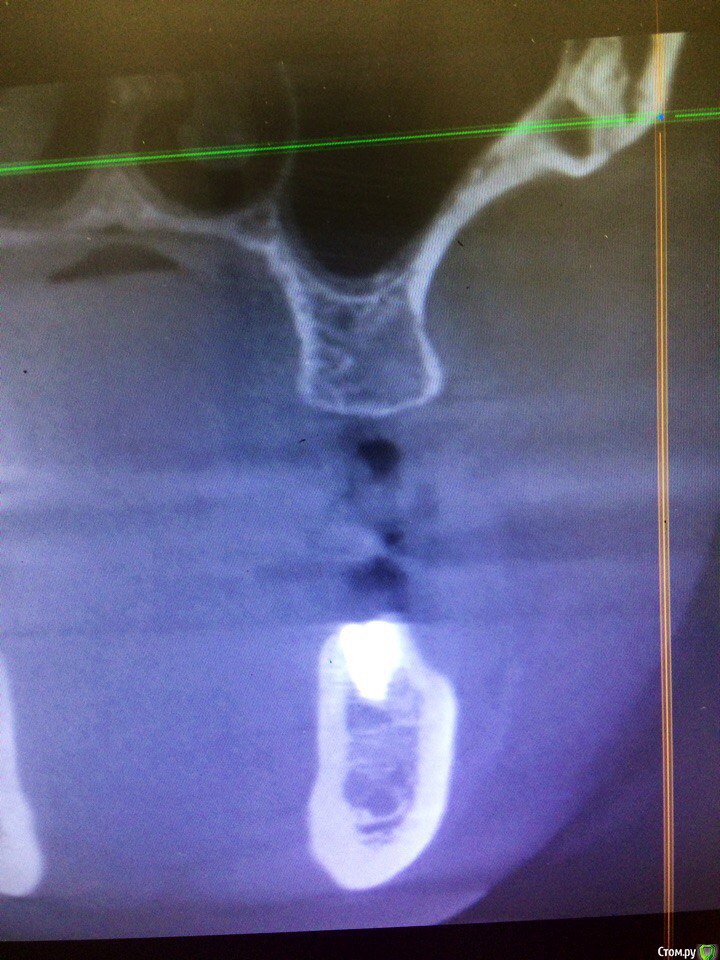

kamranchick Опубликовано 14 марта, 2017 Автор Поделиться Опубликовано 14 марта, 2017 Камранчик, если не сложно, вы это кейс не потеряйте со временем, покажите какой объем кости останется после консервации.Как и просил)высота около 9ммВвел под мембраной Resorba которая в лунки кладутся 2 Ссылка на комментарий